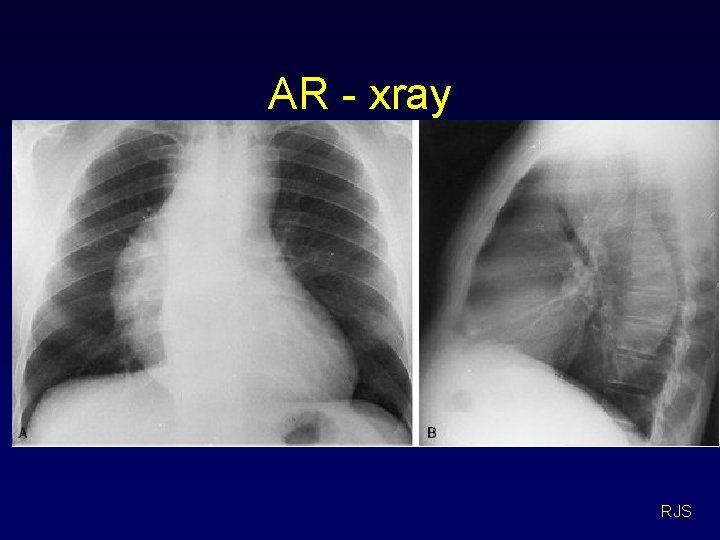

AR investigations • • ECG – LVH X-ray – abnormal aorta, large heart Echo – AR, LV dilation, dissection Angiogram – AR, LV dilation RJS

AR - xray RJS